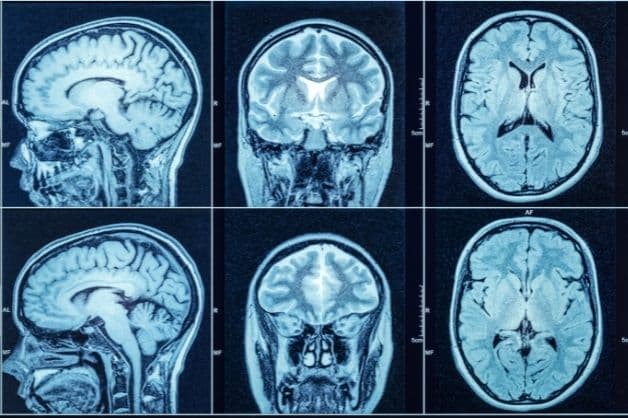

Chụp CT sọ não có thể cung cấp hình ảnh chi tiết, rõ nét các cấu trúc hình thái cũng như những bất thường xuất hiện ở vùng đầu và mặt. Thông thường, bệnh nhân được chỉ định chụp CT sọ não khi gặp các tổn thương sọ não như: u não, teo não, máu tụ, áp xe… Vậy đối tượng nào được bác sĩ chỉ định chụp, đối tượng nào chống chỉ định, cùng tìm hiểu rõ hơn các thông tin này qua bài viết dưới đây!

Sọ não là một trong những cơ quan trọng và phức tạp nhất trong cơ thể con người, chứa nhiều dây thần kinh, mạch máu và các thành phần mô não khác. Chính vì vậy, việc chẩn đoán chính xác nguyên nhân gây ra ra các bệnh lý vùng sọ nào cũng gặp nhiều khó khăn. Chụp CT sọ não là phương pháp chẩn đoán hình ảnh được coi là hiệu quả và được chỉ định trong nhiều trường hợp bệnh nhân.

Chụp CT sọ não được áp dụng nhiều kỹ thuật khác nhau để chẩn đoán các bệnh lý hoặc tổn thương sọ não